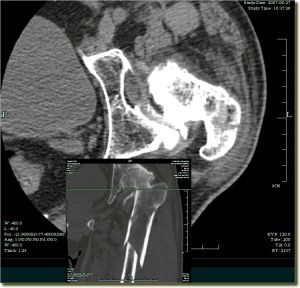

X線檢查 臨床檢查是診斷的第一步,它只能說明髖關節有問題,但最後作出診斷需用X線攝片。嬰兒出生後2~3月內,股骨頭骨骺骨化中心尚未出現,X線檢查乃依靠股骨頸的乾近側端與髖臼關係來測量。骨化中心出現後,攝片包括雙側髖關節的骨盆片可以確定診斷,攝片時將雙下肢併攏,將患肢上推和下拉住各攝一片對比測量,則變化更明顯可靠。測量方法有以下幾種:

在有條件時可套用CT或MRI檢查便可明確診斷。